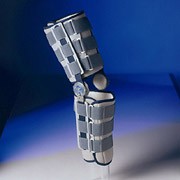

Коленный ортез Genu Arexa, 50K13

Армированный коленный ортез из легкого сплава Genu Arexa (джену арекса) 50К13 – новая разработка в ряду фиксирующих рамных конструкций. Обеспечивает жесткую стабилизацию и надежную защиту сустава. Функционально схож с ортезом 50К12 "Advantage II"®.

- Рама ортеза изготовлена из легкого и прочного сплава с защитным покрытием.

- Конструкция имеет небольшой вес и анатомический дизайн, обеспечивающий плотное прилегание и четкое соответствие контурам ноги пациента.

- При затягивании ремней проксимальное и дистальное гибкие пластиковые крылья легко подгоняются по форме ноги пациента.

- Полицентрические шарниры снабжены инновационной системой "Click2Go": необходимый диапазон движений в шарнире может быть задан с помощью ограничителей угла сгибания (6°, 10°, 20°, 30°, 45°, 60°, 75°, 90°) и разгибания (6°, 10°, 20°, 30°, 45°). Ограничители устанавливаются без дополнительных инструментов, регулировка углов осуществляется независимо.

- Мыщелковые пелоты из материала TechnoGel® создают дозированное локальное давление в области суставной щели и обеспечивают боковую стабилизацию сустава. Система "Click2Go" позволяет легко изменить положение пелотов соответственно ширине колена с помощью переходных колец.

- Рама и ремни снабжены удобными смягчающими подкладками.

- Тибиальная смягчающая подкладка устраняет избыточное давление на большеберцовую кость и препятствует вращению ортеза на ноге.

- Ортез малозаметен под одеждой.